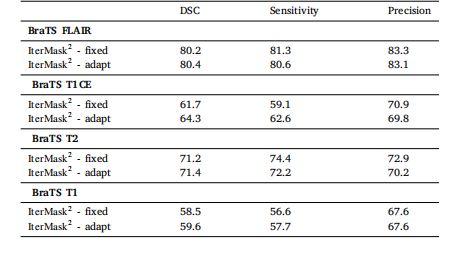

Table 5Ablation study for observing the effect of spatial and frequency masking in the 2D (top) and 3D (bottom) versionsof our model. We also show performance of our 2D model(IterMask2 ) in 3D images from BRATS (bottom) for straightforward comparison with IterMask3D, showing the gainsfrom 3D modeling.

表5 空间掩码与频率掩码作用的消融实验结果 (上表为模型2D版本的实验数据,下表为模型3D版本的实验数据) 此外,为与IterMask3D进行直观对比(以体现3D建模的优势),表中还展示了2D模型(IterMask2D)在BraTS数据集3D图像上的性能表现。